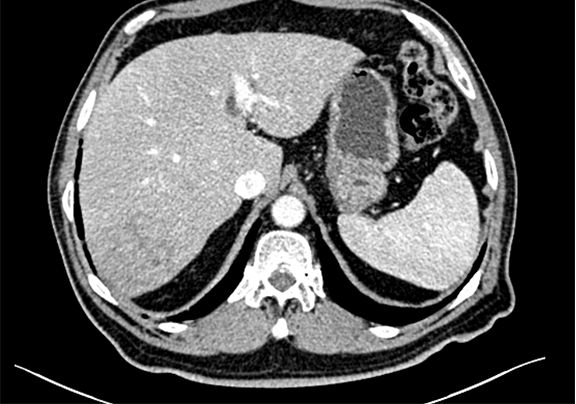

术前CT检查:动脉期

静脉期